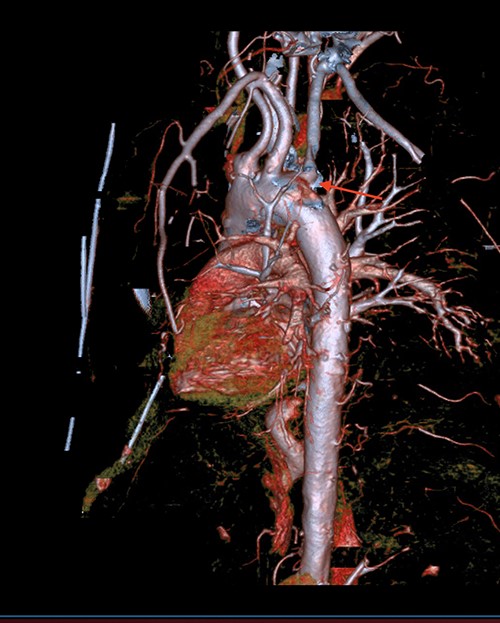

A 71-year-old male with past medical history of type 2 diabetes and hypertension presented to the emergency department at St. Joseph’s University Medical Center with severe respiratory distress. On nonrebreather, the patient’s oxygen saturation was 49%. The patient was subsequently intubated. Evaluation revealed pneumonia secondary to COVID-19 leading patient to be intubated on ventilator support for 4 weeks. During this time patient was maintained on enteral feeding through nasogastric tube, and was on gastrointestinal prophylaxis Protonix 40 mg daily for the duration of his admission. Ultimately, the patient made full recovery and was sent home; however, approximately 3 weeks later, he presented to the emergency department due to syncope. The patient experienced large-volume bright red hematemesis. He became hypotensive and was transfused three units of packed red blood cells and started on pressors. The patient was intubated and transferred to the intensive care unit (ICU) with acute blood loss anemia and hypovolemic shock. Here, an esophagogastroduodenoscopy (EGD) was performed revealing midesophageal bleed (Fig. 1). Hemostasis was achieved with clipping; however, post-procedurally, the patient again became hypotensive. Repeat EGD showed a nonbleeding esophageal ulcer with three clips in good position (Fig. 2). Computed tomography (CT) angiogram of the thorax was performed revealing an actively bleeding aberrant right subclavian artery perforating into the esophagus (Figs 3 and 4). The right subclavian artery was noted to be of normal caliber without ectasia or aneurism and the esophagus was free of any other pathology. Thoracic and vascular surgery were consulted; however, the bleed was deemed of nonsurvivable pathology due to comorbidities and current clinical status. Ultimately, the family of the patient decided to withdraw care and the patient passed.

CT thoracic showing the arch of the aorta with the take-off of the right subclavian artery (red arrow) distal to the left subclavian artery.

The aortic arch, located in the superior mediastinum, has three branches: brachiocephalic artery, left common carotid artery and left subclavian artery. The right subclavian artery, a branch of the brachiocephalic artery, travels laterally between the anterior and middle scalene muscles. However, there have been documented cases of anomalous arteries, including right subclavian, as in our patient. A left aortic arch with an aberrant right subclavian artery is the most common congenital anomaly of the aortic arch with a prevalence of 0.5–2.0%, causing the right subclavian to have an oblique retroesophageal course [5]. Our patient had an aberrant right subclavian artery in proximity to the esophagus. The ulceration, due to either prolonged nasogastric tube insertion or COVID-19, coupled with the aberrant artery proved to be catastrophic for this patient and ultimately led to his demise.